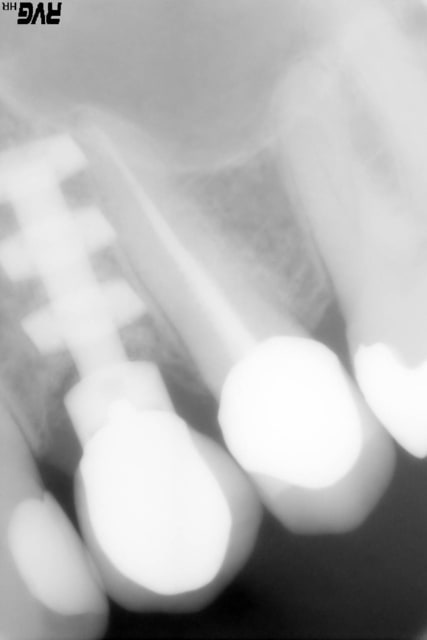

Patiente présente une perte alvéolaire de la table externe suite à fracture radiculaire.

ici , fracture 13-14:

rog avec membrane titane